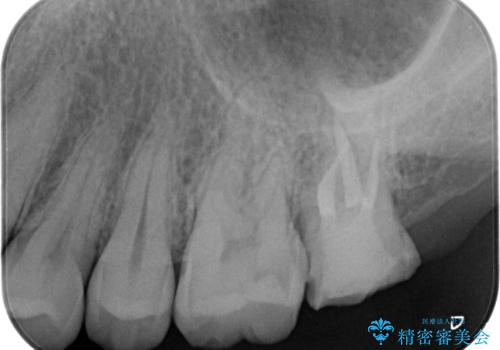

- 銀歯を良いものに変えたいとの事で来院。

過去に根の治療もされている歯だが土台が粗造なため根の治療からやり直しを行いゴールドクラウンにて治療を行いました。

また手前のはに虫歯があったためセラミックの詰め物で治療しました。